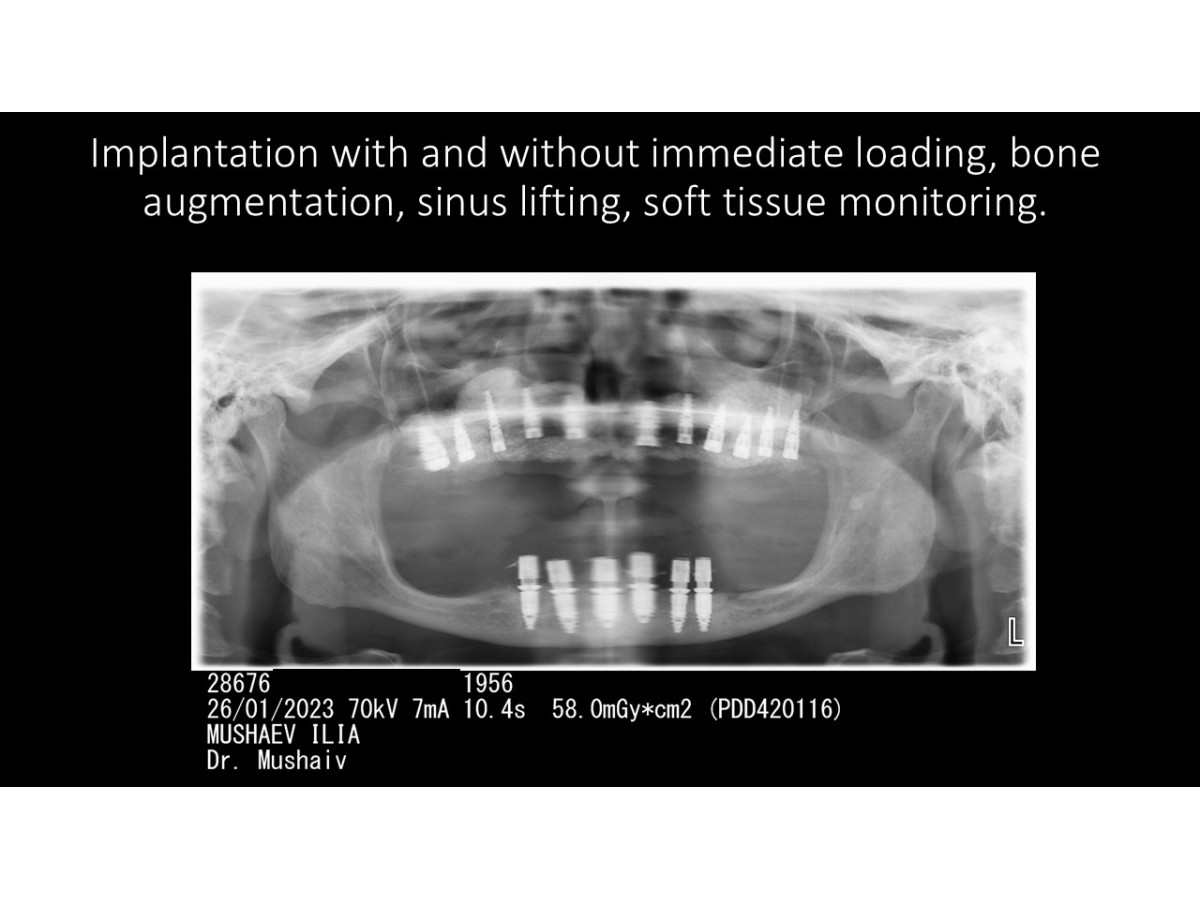

Clinical case: Dental implantation with & without immediate loading, bone augmentation, nasal and sinus lifting, soft tissue monitoring.

Dentist: DDS PhD Ilia Mushayev/Sidhedent, DMi (Israel)

Clinical case, dental implantation